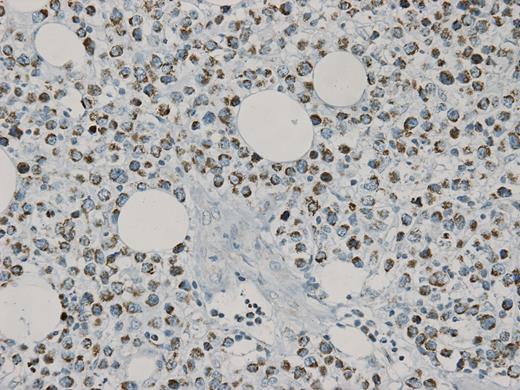

MCT4 stain (40x) demonstrating exclusive staining of stromal cells, sparing cancer cells